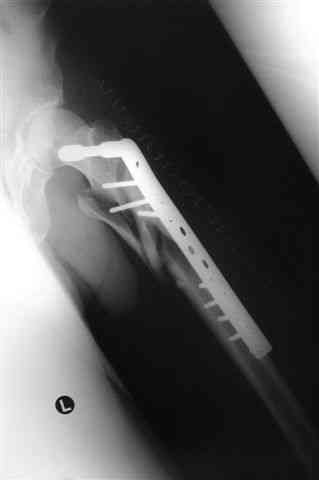

Бедро фиксировал длинной DCS.

По типу бриджинг плэйтин, крюком удалось низвести малый вертел и фиксировать винтом для восстановления медиальной стенки.

> Бедро фиксировал длинной DCS.

А почему не гвоздем закрыто?

ET>> Бедро фиксировал длинной DCS.

AC>А почему не гвоздем закрыто?

Изначально планировался длинный гамма гвоздь , но набор заказывается обычно из Йоханнесбурга, а в этот раз все совпало с новогодними празднованиями и вся жизнь была *парализована* новогодней фиестой:-((, поэтому безуспешно прождав 3-4-5 дней обещанной доставки зафиксировал пластиной- жаль, что так всй случилось У местного

Страйкера сервис ненавязчивый :-))

Снимки бедра и голеностопа еще не сфотографировал, обязательно представлю на форум

В приложении отправляю послеопер. снимки бедра и лодыжки обсуждаемого вчера больного.